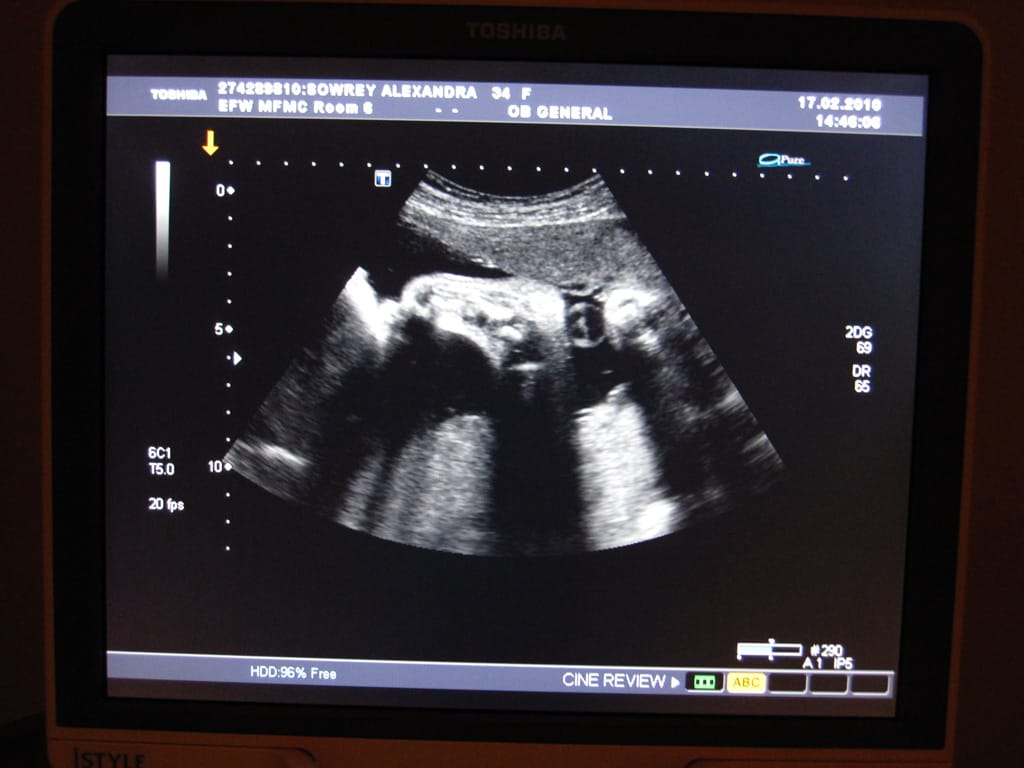

Yesterday, we went to the Maternal Fetal Medicine clinic at the EFW at the Foothills medical complex. Alex underwent a near hour-long ultrasound, drawn out mostly due to a perinatologist-in-training (getting backup from a well-trained sonographer) and a very mobile (hence, uncooperative) baby. Most of the ultrasound was measurement, checking size (the kid’s already clocking in at nearly 6 lbs).

It was the latter part of the exam that intrigued me — it was something I hadn’t seen before. The operators (including Dr. Greg Connors, the head perinatologist in Calgary) were doing a doppler test on blood flow in Choo Choo’s brain. At the time, it was intriguing to watch, though I didn’t really understand what was going on.